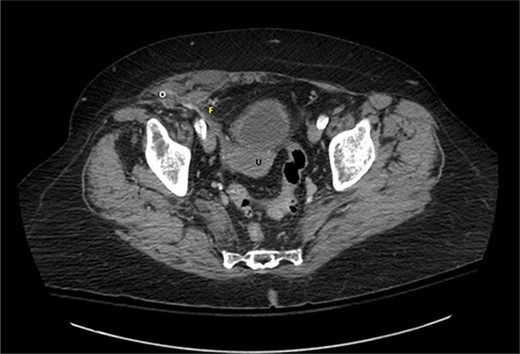

A 76-year-old Caucasian female presented to the emergency department for evaluation of 3 days of progressively worsening abdominal pain. The pain was characterized as an ache, originated in the right lower quadrant and radiated to the bilateral upper quadrants. Past medical history was significant for obesity (BMI 31 kg/m2), chronic obstructive pulmonary disease, gastroesophageal reflux disease, hypertension, hypothyroidism, heart failure with preserved ejection fraction, atrial fibrillation, and scleroderma. Pertinent surgical history included a dual-chamber pacemaker and tubal ligation. She was anticoagulated with apixaban. Physical examination revealed right lower quadrant tenderness to palpation and rebound tenderness without a palpable abdominal bulge. Contrast-enhanced computed tomography of the abdomen and pelvis did not clearly demonstrate the appendix, but rather a ventral hernia in the lower right quadrant. The fascial defect was lateral to the rectus abdominis, superior to the inguinal ligament, and inferior to the arcuate line. The defect measured 3.6 × 2.0 cm and involved the transversus abdominis and internal oblique muscle aponeuroses while the external oblique remained intact, consistent with Spigelian hernia (Fig. 1). There was an oblong structure extending parauterine into the hernia sac with a small amount of free fluid suggestive of the right ovary and fallopian tube (Fig. 2). Considering these findings and appropriate cessation of anticoagulation, the patient was taken for diagnostic laparoscopy and transabdominal preperitoneal hernia repair.

Axial view of contrast-enhanced computed tomography of the abdomen and pelvis demonstrating the right fallopian tube (F) attached to the uterus (U) extending into the Spigelian hernia defect containing the right ovary (O).